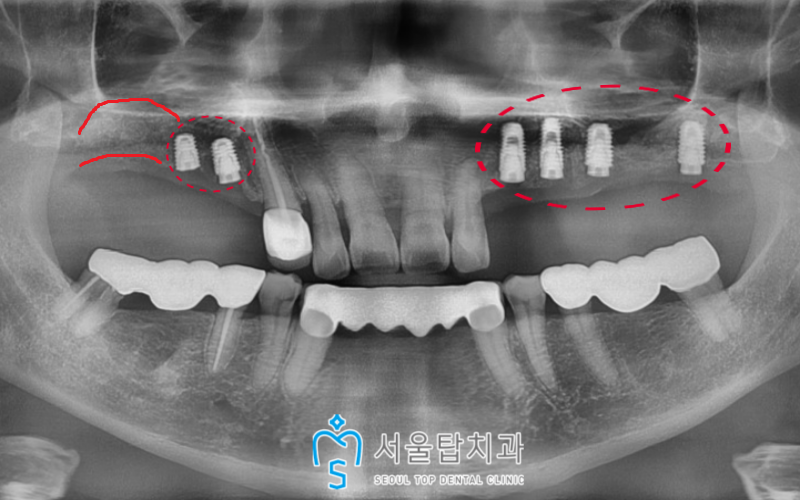

왼쪽에 부러진 치아를 2개 발치하고

기존 상실된 부위와 함께

임플란트 식립을 진행한 모습입니다.

오른쪽은 작은 어금니 자리(#14, 15)는

바로 식립을 진행하였으며

큰 어금니 부분은

상악동 거상술과 뼈이식을 진행하였고,

기반이 갖추어지고 난 이후

임플란트를 식립 할 예정입니다.

(환자분의 경우 6개월 후)

지금은 치아 뿌리 역할을 하는

인공치근인 픽스처만

식립되어 있는 상황인데요.